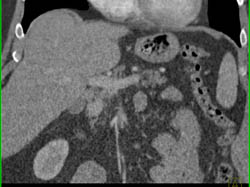

Atypical Focal Nodular Hyperplasia (FNH)